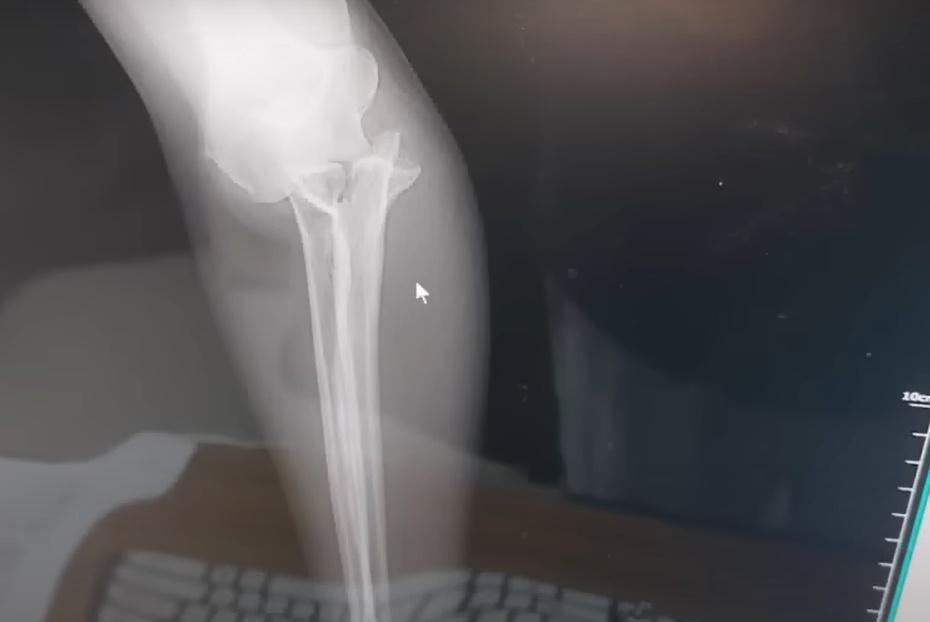

事後Beth被帶到酒店的前台敷冰,由於傷口不斷腫脹,便被送到醫院檢查,透過X光機發現她的手臂骨折,隨即要接受手術,以鋼板和骨釘螺絲固定骨頭。Beth又提到,園方原先承諾支付一半的醫療費用,不過後來不再回應夫婦的聯絡,直到外國傳媒報道事件,最近終於收到園方的賠償。Beth與丈夫沒有將這個意外歸咎於大象,但勸誡其他遊客到峇里島接觸大象時要注意風險。Beth提醒:「這將是一條漫長的康復之路。」